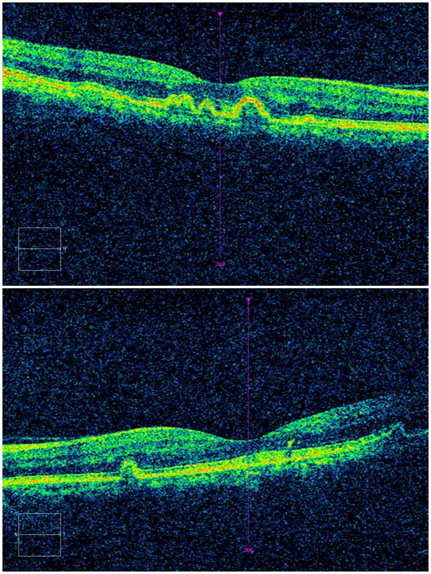

A 45-year-old female patient, who had been followed up with a diagnosis of age-related macular degeneration for two years in another hospital, presented with complaints of blurred vision and metamorphopsia, more severely in her right eye, which she said to have started two months ago. The best corrected visual acuities were 0.1 in the right eye and 1.0 in the left eye with Snellen chart. There was no color vision deficiency. There was no complaint of nyctalopia, photosensitivity, or hemeralopia. Visual acuities in light and dark environments were equal. There was no pathology in anterior segment examinations and intraocular pressures were 16 mmHg and 15 mmHg in the right and left eye, respectively. Fundus examination revealed bilateral, subretinal, round and yellow-white flecks with scattered localizations in the fovea, macula and peripheral retina. The diameter of the lesions was approximately one to two times the diameter of the retinal artery. Some of the lesions were merged with each other. Flecks were mostly concentrated in the macula and midperipheral fundus however were rare in the peripheral fundus. Optic nerve heads and retinal vessels were normal, and there were no signs of ocular inflammation (Figure 1). In fundus fluorescein angiography, flecks showed hyperfluorescent staining with well-demarcated borders in early and late phases and there were no signs of choroidal neovascularization or leakage (Figure 2). In optical coherence tomography, there were hump-shaped lesions which have medium degree internal reflectivity at the level of retinal pigment epithelium along with hyporeflective dome-shaped pigment epithelial detachments. No subretinal fluid was observed (Figure 3). There was not any visual field defect. The patient had no other systemic diseases and was not on any medication. There was no family history of retinal pathology. No pathology was found in the ophthalmological and systemic examination of her first-degree relatives. The patient was consulted for genetic diseases, and no genetic disease was found. With these findings, the patient was diagnosed with an atypically distributed fleck case with multiple retinal pigment epithelial detachments and no treatment was recommended. No progression was detected and visual acuities were stable during the 12-month follow-up.

Figure 3 Hump-shaped lesions which have medium degree internal reflectivity at the level of retinal pigment epithelium along with hypo reflective dome-shaped pigment epithelial detachments.